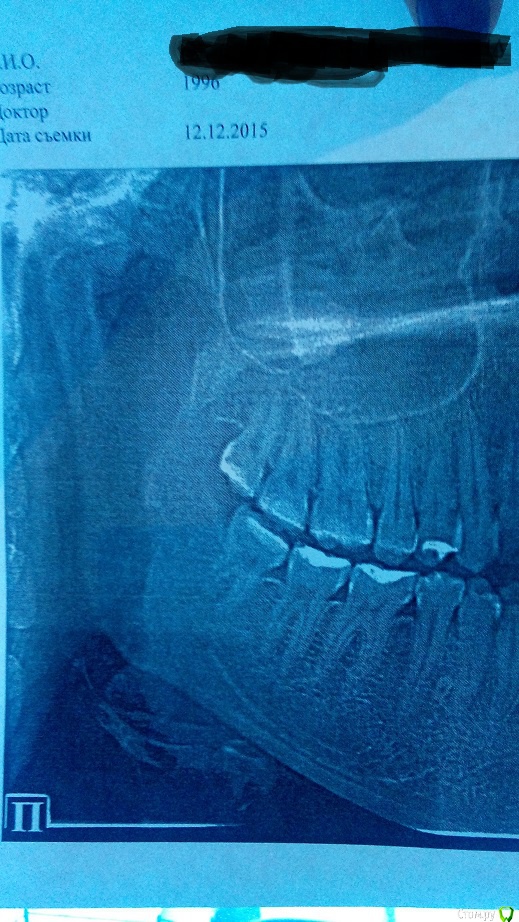

Ситуация следующая,в сентябре сделала снимки и ортодонт сказал,что головка сустава смещена

сегодня 12 декабря сделала опг снова,к сожалению сустав там плохо,как мне кажется

так же интересует удаление восьмых зубов в моем случае ,так как один хирург сказал,что отказывается удалять мне правую восьмерку ( а с суставом проблема к слову справа) ,так как повредит мне

и со слов остеопата,если удалять восьмерки то будут проблемы